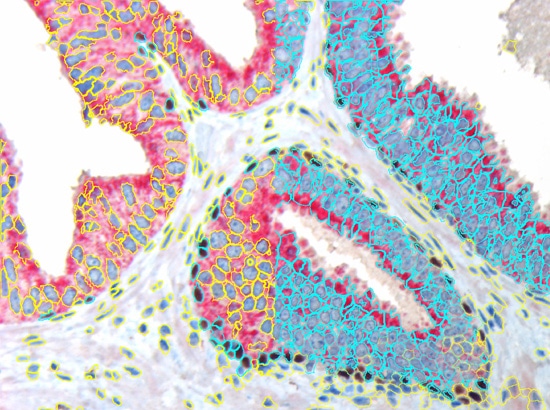

The nuclear segmentation algorithm is highly efficient in difficult situations in tissue and can be set with two values only - mean nuclear size and nuclear channel background threhshold. The cell compartment algorithm provides a large amount of flexibility with a few simple settings (see below, yellow=segmented nuclei, blue nuclei positive for DAB or cytoplasm positive for Permanent Red marker).